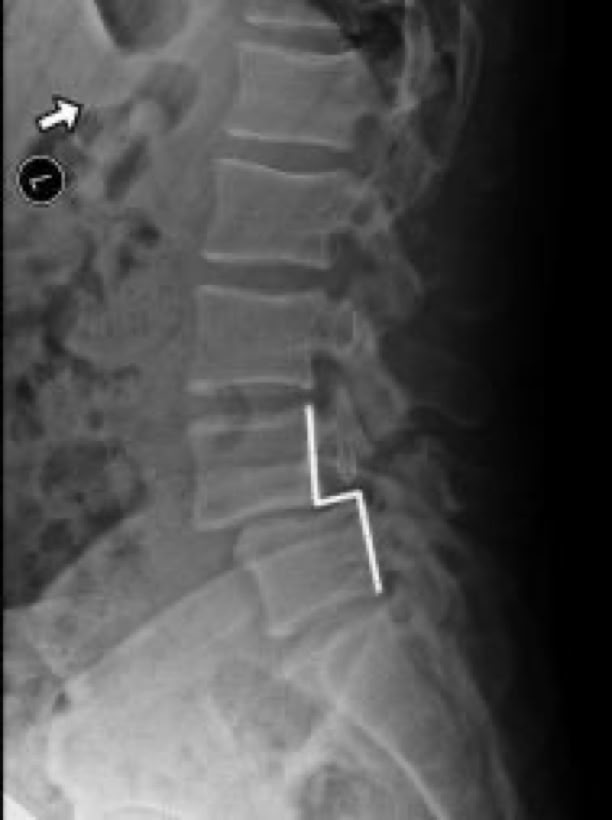

Spondylolisthesis is most commonly found in the lumbar spine as these levels bear the most weight. To assess instability, we take x-rays of a patient bending forward (flexion) and bending backwards (extension). Normally there would be no motion. The more motion seen between flexion and extension x-rays across an injured level, the greater the patient’s symptoms usually appear.

X-RAY SHOWING A PARS FRACTURE DEFECT

THE WHITE OUTLINE SHOWS THE SLIPPAGE.